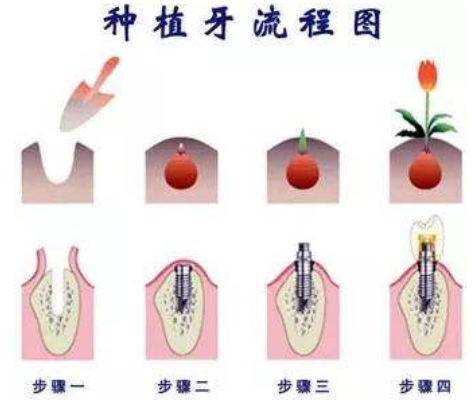

最后一种就是种植牙,种植牙不是真的能够种出一颗真牙,它其实是一种高度仿真的牙齿修复技术。种植牙有一颗类似钉状的金属种植体,在缺失牙齿的位置上把这根“牙根”埋植到牙槽骨内充当牙根的作用,再以此为基础镶上假牙,种植牙装一颗牙多少钱主要看缺牙者选择的种植牙材料而定,价格大致在七千多到一万多不等。

种植牙的优点在于:

1、原理科学:种植牙将咀嚼压力通过人工牙根(种植体)传递至牙槽骨,生物力学原理与天然牙相同,能承受强大的力量;能够有效的提高咀嚼效率、很好地恢复牙齿功能,咀嚼功能大大优于其他传统活动和固定假牙。》》》推荐阅读:在廊坊,种植牙大概多少钱一颗?

2、健康的牙齿可以完全保留,不需要磨掉邻近健康的牙齿。种植牙有自己独立的牙根固位,不需要依附邻牙来固位,健康的牙齿可以完全保留,不需要磨损邻近健康的牙齿,还可以防止由于缺牙导致邻牙的移位或牙齿松动。

3、稳固牢靠:种植牙具有很强的固位力与稳定性,不使用传统镶牙的卡环或牙套,人工牙根牙槽骨紧密结合,像真牙一样扎根在口腔里,具有很强的固位力与稳定性,感觉就像自己天生的牙齿。

4、舒适美观:不需要活动假牙必备的基托与卡环,没有大面积塑料基托导致的味觉迟钝与不舒适感;烤瓷牙的牙冠材料可以选择,烤瓷牙的形态、颜色可以根据就诊者的脸型、其他牙齿的形状与面部肌肤的颜色来进行制作,达到整体协调和美观的最佳效果,面部形态表情自然。

5、种植牙使用寿命相对比较长,可以避免反复更换假牙的麻烦。种植体选用对人体相容性极好的生物材料,种植牙对人体不产生任何不良的副作用。

6、清洁卫生,外型美观:就像天生牙齿一般,说话时面部表情就像原来一样自然,使用起来比较方便,而且有利于保持口腔的清洁卫生。》》》推荐阅读:在廊坊,种植牙可以用多少年?

7、保护牙槽骨:人工种植牙则无移动或咀嚼功能不好的情况,而且在植入部位的牙槽骨,种植牙对牙槽骨形成功能性刺激,能保护牙槽骨结构,避免其萎缩。

8、创伤小:种植牙手术是一个较小的牙槽外科手术,采用局部麻醉,术后即可进食,几乎无痛苦,并且如果患者局部情况良好,可以进行不翻瓣的微创种植,创伤更小,恢复更快。

缺点在于:种植牙不是所有人都适合做,全身情况良好,身心健康、骨骼和牙齿发育已定型者的成年人适合做种植牙,如有出血性疾病、高血压、心脏病、糖尿病等全身疾病,在该病治疗稳定后,方可接受牙种植术。